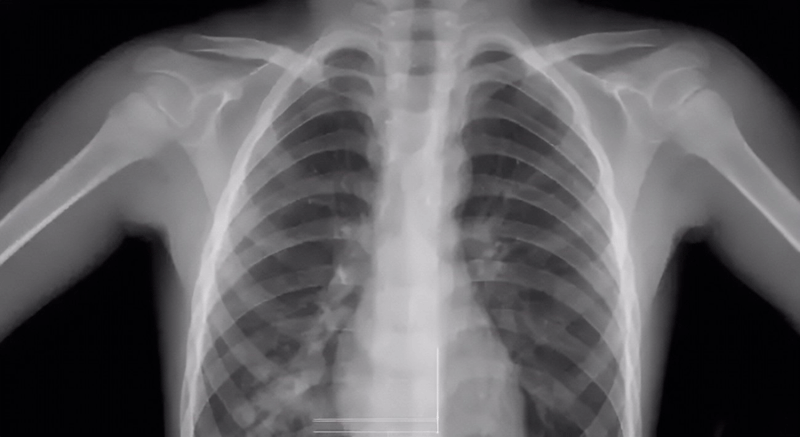

关于胸透检查报告

做胸透检查可以查出的项目非常多,它是通过X射线穿透人体的不同层度结合荧光成像来分析人体某部位存在的异常。胸透检查报告的主要内容有:显示肺部是否有疾病、心脏是否有异常、胸膜有无问题、胸壁纵隔、肋骨有无受损、支气管疾病等。

胸透检查报告常见结果分析:

1、两肺未见明显活动性病变:说明肺部非常健康,无病变出现;

2、胸廓无异常,两肺纹理清晰:说明胸部或肺部没有任何异常;

3、两上肺可见斑点状钙化:说明患者以前可能在不知情的情况下得过结核病,但没有发现就自愈了;

4、两肺门影不大:说明肺部和器官都很健康,心脏功能也很正常,若有心脏病,可能会引起肺门水肿;

5、气管、纵隔无偏移:说明颈部和胸腔内没有出现肿瘤或任何异物,如果有肿瘤或异物的话会把气管和纵隔推偏,看起来位置就会发生错位;

6、两肋膈角锐利:说明胸腔内没有积水或渗出液,当出现炎症或结核等病变时会引起积液渗入到胸腔内,使肋膈角变得模糊圆钝;

7、心影形态大小未见明显异常:说明心脏是健康的;

8、膈面光整:腹腔里面的各个小组织没有出现穿孔,因为穿孔会让气体外泄,使膈面下有黑影。